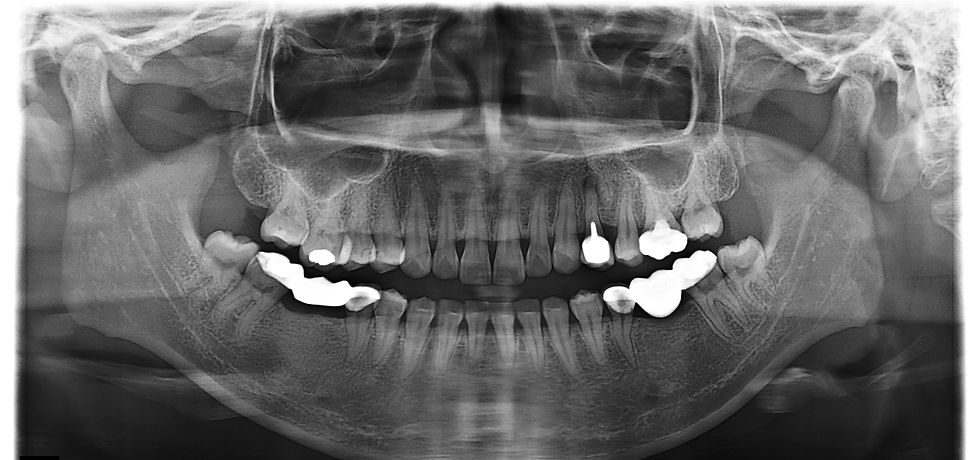

Figure 1. Initial Situation, the 27 y.o. patient presented 2-piece metal post-core with PFM crown. The #24 tooth was dignosis with asymtomatic periapical lesions with existing of possible medicated material in canal orifice.